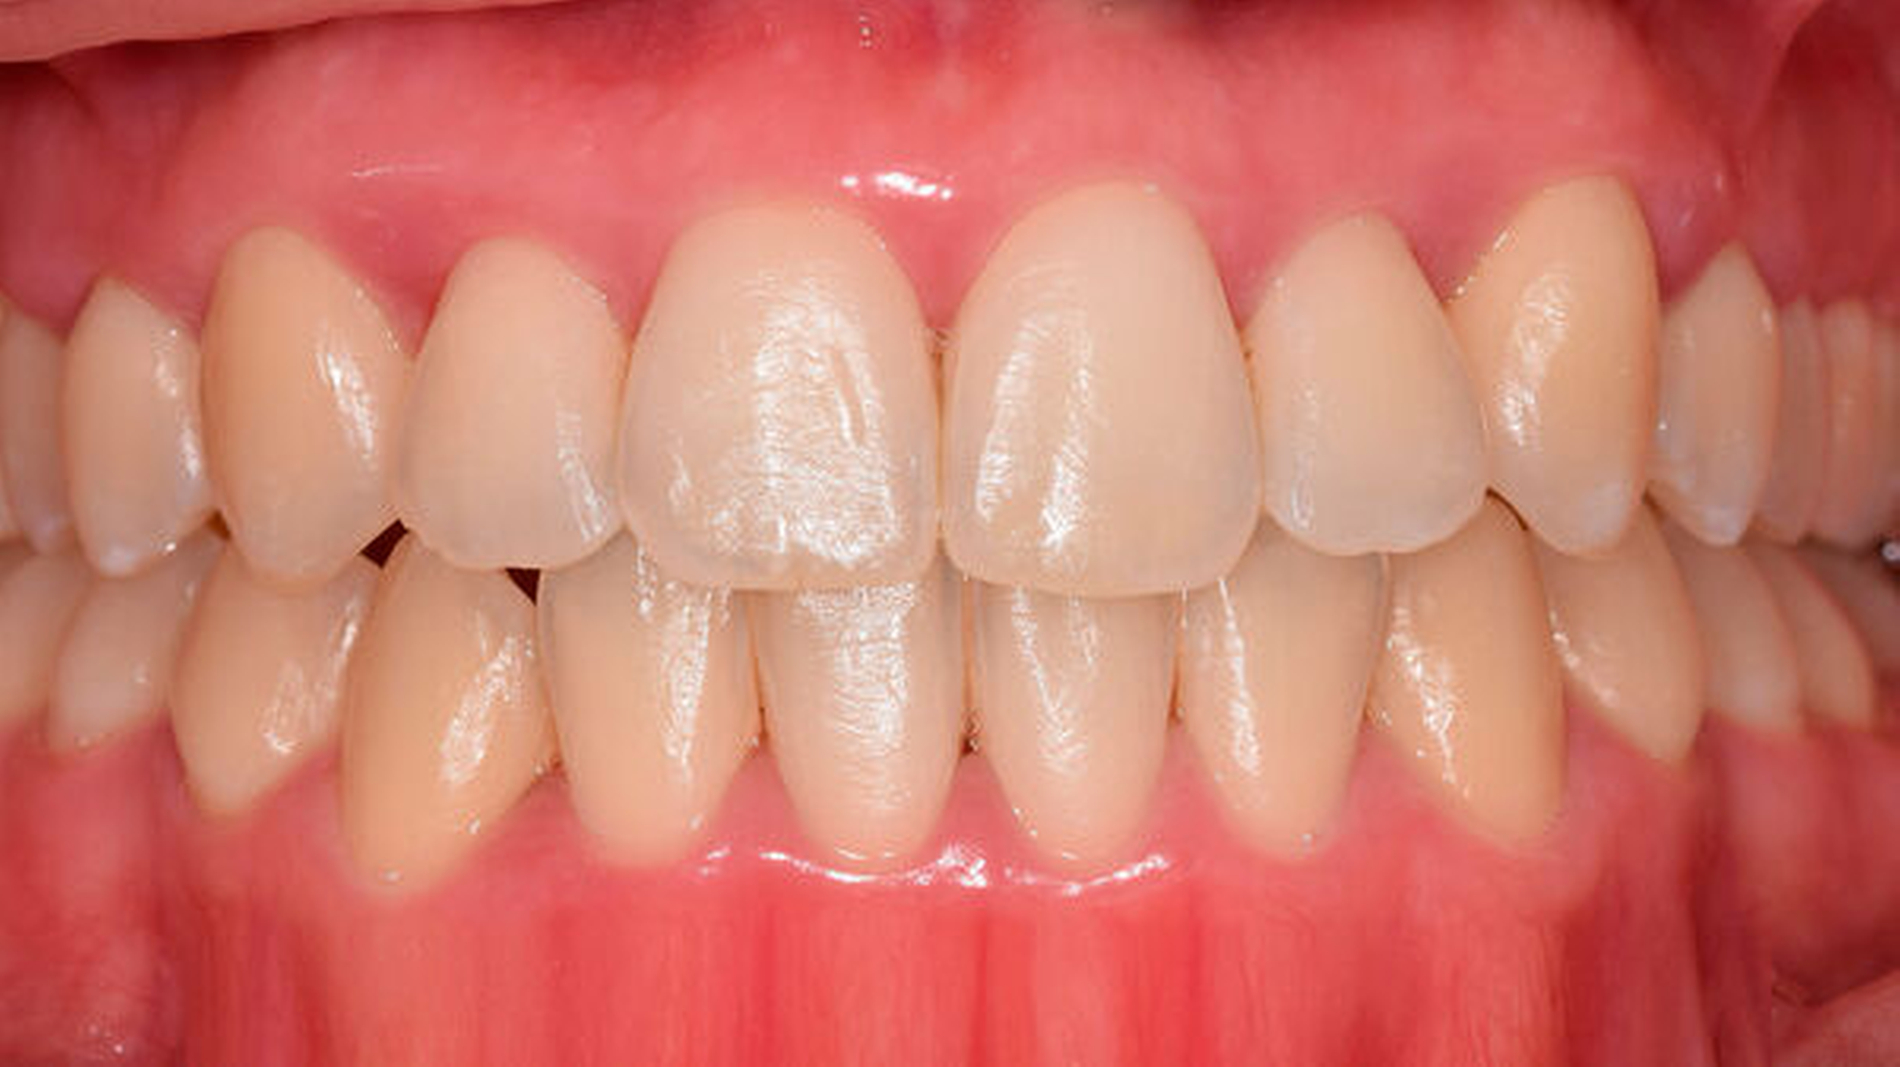

Die subgingivale Instrumentierung hat zum Ziel, durch die Entfernung harter und weicher Beläge von der Wurzeloberfläche die Weichgewebsentzündung zu reduzieren. Eine Zielgröße der Behandlung ist „Pocket Closure“ (geschlossene Taschen), was als Taschensondierungstiefe (TST) ≤ 4 mm und Abwesenheit von Bluten auf Sondieren (BOP) definiert ist. Ein RCT mit 169 Patienten mit einem dreimonatigem Follow-up und weitere elf prospektive Studien (n = 258) mit einem sechsmonatigem Follow-up wurden analysiert. Erfasst wurden die postoperative Reduktion der TST (primäre Zielgröße) und der prozentuale Anteil von geschlossenen Taschen (sekundäre Zielgröße). Die Evidenz zeigte eine durchschnittliche Reduktion der TST von 1,7 mm nach sechs Monaten, einen mittleren Anteil an geschlossenen Taschen von 74 Prozent und eine durchschnittliche Reduktion des BOP um 63 Prozent. Tiefere Taschen (> 6 mm) zeigten eine größere mittlere Reduktion der Taschensondierungstiefe von 2,6 mm (Abbildung 2).